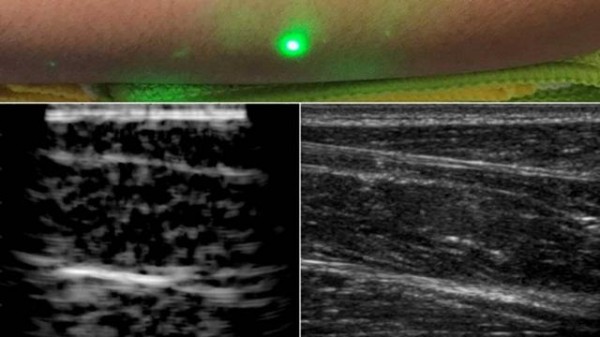

麻省理工學院設計了一種新方法,并使用激光超聲產生了第一批圖像。這項新技術不需要與身體接觸即可看到患者體內。該技術使用對眼睛和皮膚安全的激光系統。系統中的一個激光可以遠程產生聲波,通過身體反彈。第二個激光遠程探測反射波,這些反射波被轉換成與傳統超聲波相似的圖像。

在測試中,研究人員用半米外聚焦在志愿者身上的遠程激光,掃描了幾位志愿者的前臂,并能夠觀察到皮膚以下6厘米深的組織特征,例如肌肉,脂肪和骨骼。這些圖像可與傳統超聲相媲美。

研究小組使用1550nm激光,這種波長被水高度吸收,對眼睛和皮膚都是安全的。激光產生清晰可見的脂肪,肌肉和組織邊界的圖像。該團隊計劃改進該技術,并對其進行完善以解決功能上的缺陷。他們還希望提高激光的探測能力。在未來,他們希望改進現有設備,成為便攜式設備。